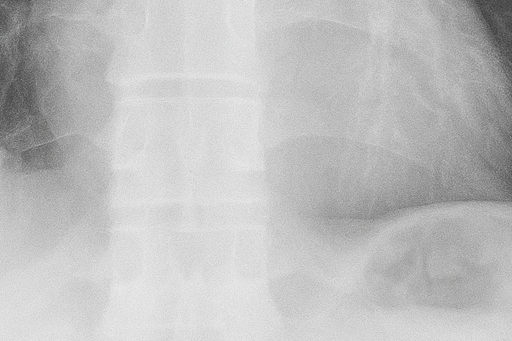

(2) 흉부 X선 검사

흉부 X선 촬영은 가장 기본적이고 신속한 진단 방법입니다. X선 영상에서 공기가 찬 부위는 검게 보이며, 허탈된 폐는 중심 쪽으로 쪼그라든 형태로 나타납니다. 이를 통해 폐 허탈의 범위와 기흉의 크기를 확인할 수 있습니다. 그러나 폐 상부의 작은 공기집(bleb)은 X선으로 잘 보이지 않아, 필요한 경우 흉부 CT 검사를 시행합니다.